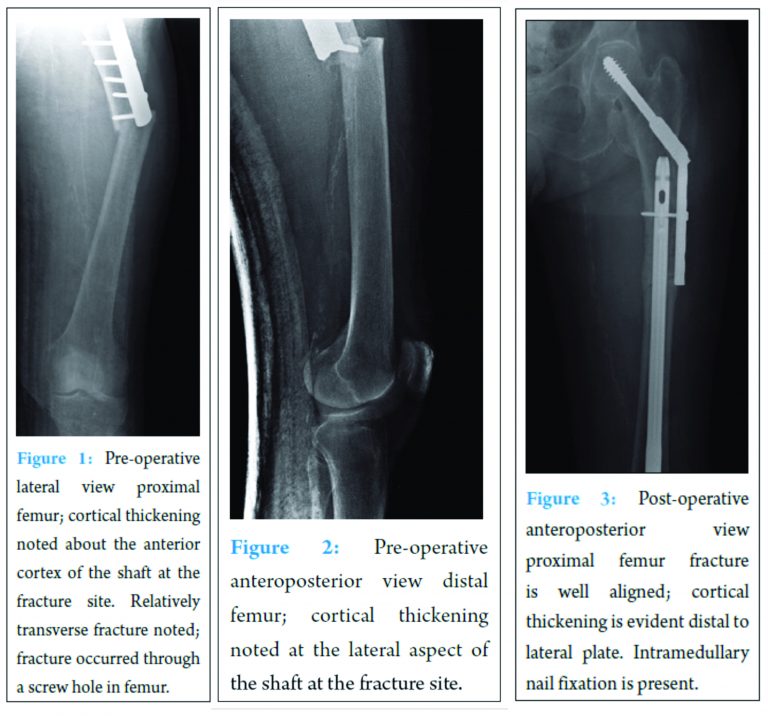

Radiographs obtained in the ED revealed a left-sided femoral shaft fracture at the distal aspect of the five hole lateral plate and screw fixation of the previously applied five hole side plate. Of note, the periprosthetic fracture demonstrated cortical thickening at the fracture site of the lateral femoral cortex, lack of comminution as well as a transverse appearance [Figures 1,2].

The patient was taken to the operating room the next day for retrograde placement of an intramedullary nail of the left femur with revision of left intertrochanteric femur fracture fixation. The five bicortical screws were removed from the sliding hip screw side plate so that the intramedullary nail could be inserted across the fracture site. The lag screw and side plate were maintained. The nail was interlocked with two screws distally and proximally. The two proximal interlock screws consisted of one anterior to posterior screw and another lateral screw through the side plate and the interlock hole in the nail. [Figure 3].